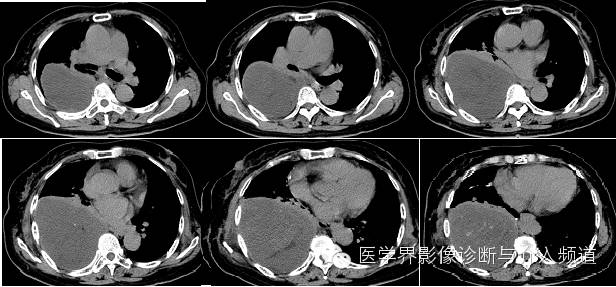

【影像图像】

【影像学表现】

右侧胸腔内见巨大囊性占位,内夹杂少许小片状脂肪及点状钙化灶。内可见分隔。增强动脉期内见血管影走形,静脉期可见病变轻度强化,CT值约为30 Hu,内分隔强化明显。